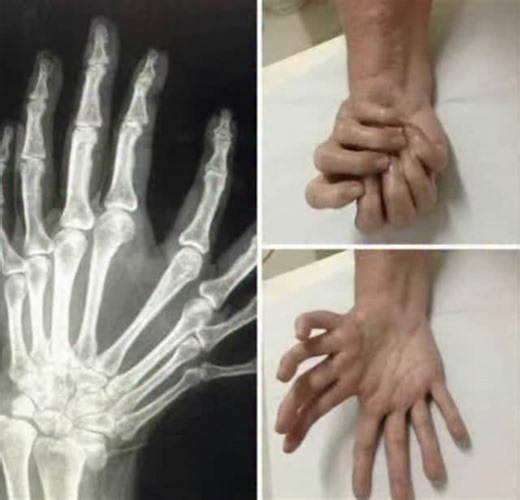

Movement Disorder - Congenital Mirror

Mirror Hand Syndrome - Mirroring